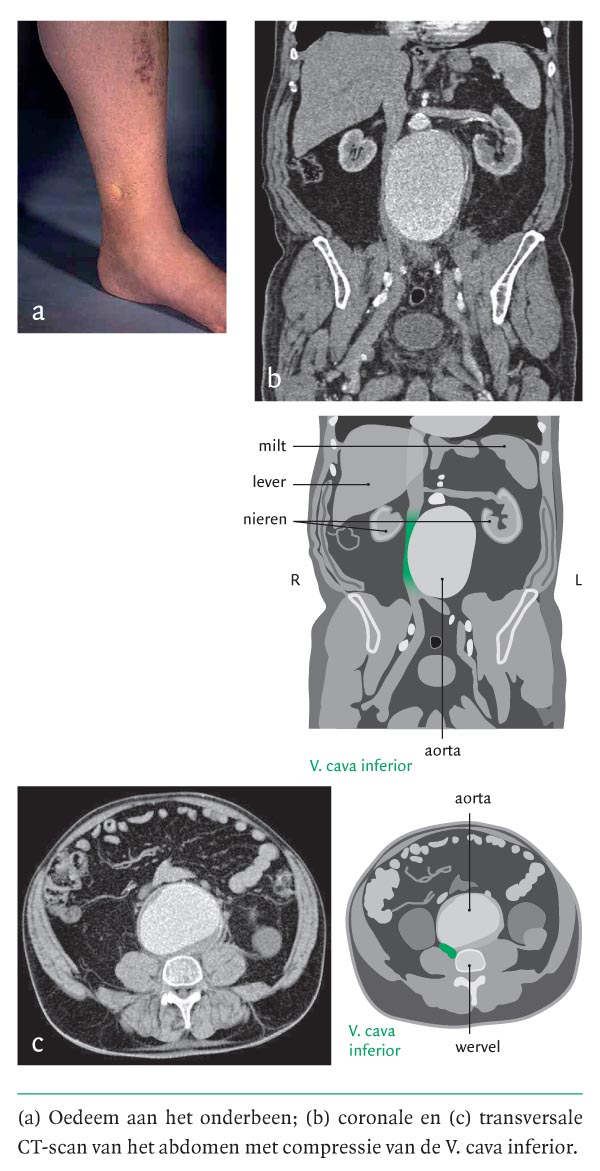

Een 76-jarige man had progressief oedeem aan beide benen. De symptomen waren 4 weken tevoren begonnen na een soort griepaanval met vage rugpijnklachten. Patiënt had chronische obstructieve longziekte en een goede cardiale restfunctie na een eerder myocardinfarct. Hij had geen klachten passend bij hartfalen. Als medicatie gebruikte hij sedert enkele jaren zonder problemen acetylsalicylzuur, nifedipine, simvastatine en bronchodilatatoren. Bij lichamelijk onderzoek werd een adipeuze man gezien met een bloeddruk van 130/85 mmHg. De centraalveneuze druk was niet verhoogd. Beide benen waren strak gespannen en oedemateus (figuur a). Over de longen werd enig crepiteren gehoord. Er was geen…